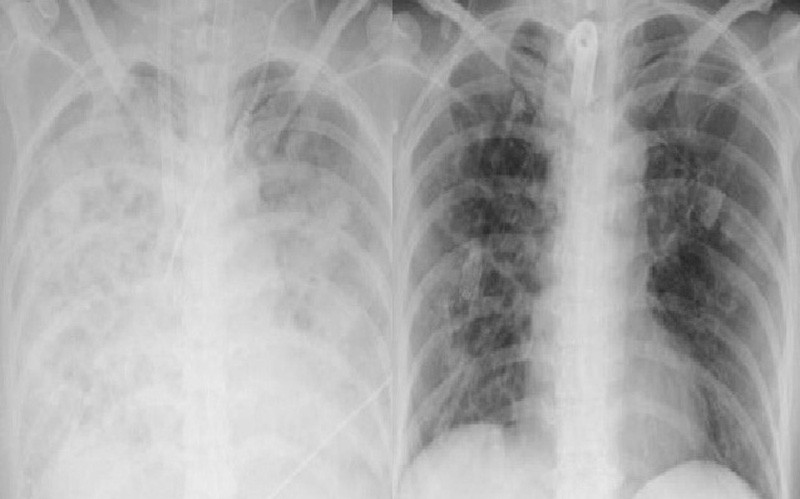

Là bác sĩ trực tiếp điều trị cho bệnh nhân, ThS.BS Nguyễn Bá Cường - Trung tâm Hồi sức tích cực, Bệnh viện Bạch Mai chia sẻ, khi vào trung tâm, tình trạng bệnh nhân rất nặng nề, sốt cao liên tục, sốc nhiễm khuẩn nặng, oxy máu giảm rất thấp, X-quang phổi mờ trắng xóa cả 2 bên phế trường, test nhanh cúm B dương tính.

Tại Trung tâm Hồi sức tích cực - Bệnh viện Bạch Mai, bệnh nhân được điều trị kháng sinh, kháng virus, thở máy và lọc máu hấp phụ. Soi phế quản có hình ảnh nhiều giả mạc lấp kín lòng phế quản 2 bên. Xét nghiệm PCR dịch phế quản cho thấy cúm B kèm bội nhiễm tụ cầu vàng.